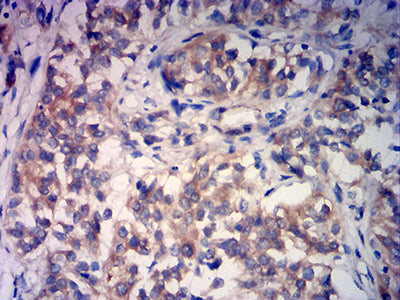

分类: 科研抗体货号: 32186别名: PTA1; DNAM1; DNAM-1; TLiSA1应用: IHC,FCM反应种属: Human

分类: 科研抗体货号: 32185别名: PTA1; DNAM1; DNAM-1; TLiSA1应用: IHC,FCM反应种属: Human